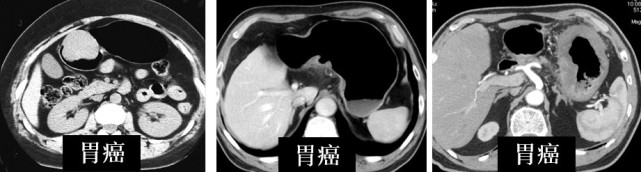

图片(异病同征示例)

这一排是胃的肿瘤,有胃肠间质瘤GIST、胃癌、平滑肌瘤,看起来都是球形的,但是它们是完全不同的病,治疗方法也完全不一样。

图片(同病异征示例)

这一排则都是胃癌,左边长得像球,中间的像个火山口,右边的则是整个弥漫的增厚,所以同样的肿瘤也可能长成不一样的形态。

这个时候影像医生就需要结合患者症状、病史和各种检查结果再去做进一步的判断。所以影像科医生是诊断医生,而不是只看片子的。如果有影像医生询问您相关的病史,是为了得到一个准确的判断,大家一定要详尽如实地跟医生们介绍。